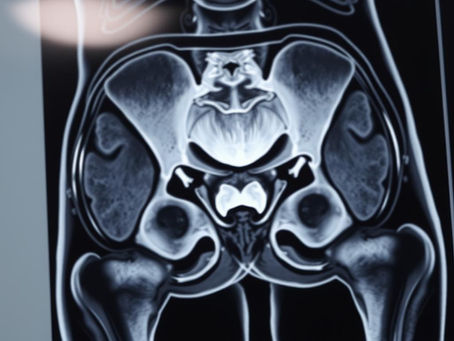

MRI for hip pain: when imaging can help identify labral tears or arthritis

Explore the benefits of MRI for hip pain diagnosis. Our Ultimate Guide covers imaging, diagnosis, and treatment for hip pain relief.